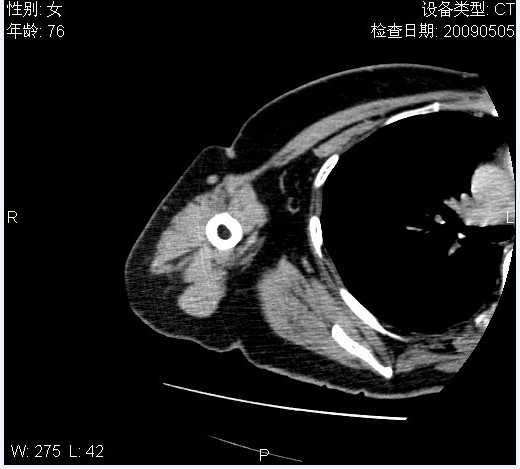

标题: CT19811:女,76岁,右上臂肿物1个月 [打印本页]

标题: CT19811:女,76岁,右上臂肿物1个月

使用了造影剂,可惜效果不太好

右肱骨上段软组织内见梭形低密度影,边界清楚,最长径约54mm.

病理结果:脂肪瘤。术中见肱骨骨膜受侵,有出血,量不详。

当时诊断意见:右肩三角肌内蔓状血管瘤(先天性动静脉瘘)。

本人对病理结果有个疑问:单纯的脂肪瘤内为什么有条状软组织影,那应该脂肪肉瘤才对啊?

该病例增强效果欠佳,由于经验欠缺,我们注射对比剂是由下肢足背静脉给药。注速2.0。虽然如此,但我们可以看到肿块内部条状软组织影是强化的,而且是连续的,并可见供血动脉是由腋动脉的其中一支即肩胛下动脉分出。从这些征象我们可以得出诊断:蔓状务血管瘤。

可病理偏偏为脂肪瘤,我怀疑取材有问题。因为蔓状血管瘤异常扩张的静脉外周是脂肪成分,它可以侵犯肌组织及骨骼。当取材于外周,那当然是脂肪瘤。此时我认为临床的最终诊断不应单从病理出发,应该综合考虑。